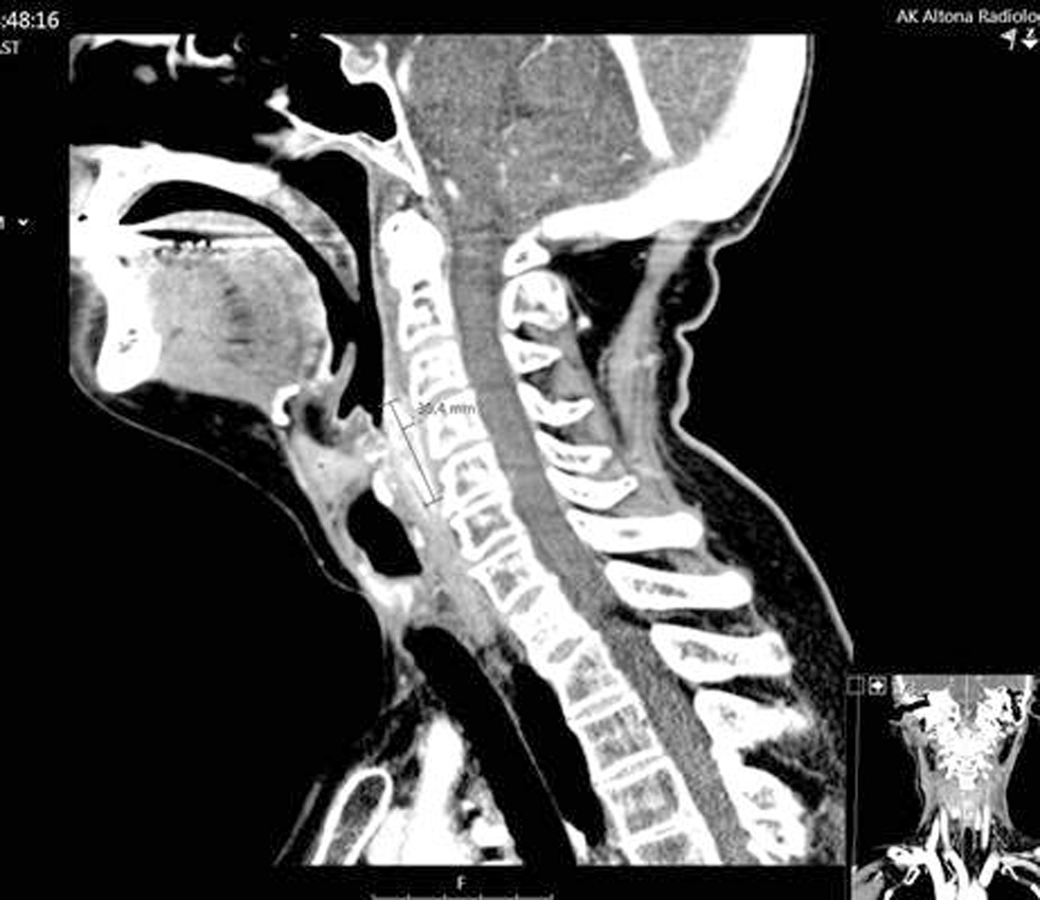

1. Im CT des Halses ist der zirkulär wachsende Tumor am proximalen Ösophagus gut zu sehen. 1. Im CT des Halses ist der zirkulär wachsende Tumor am proximalen Ösophagus gut zu sehen.